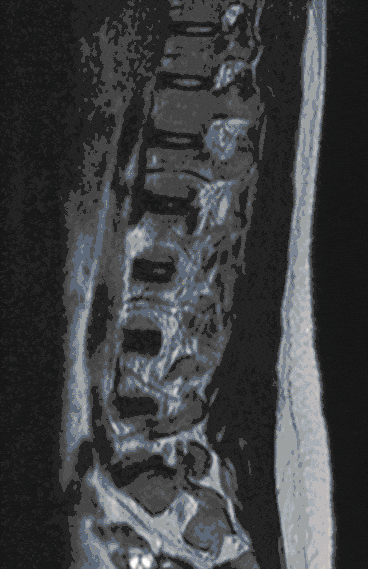

Herniated Disc

Herniated discs are among the degenerative spinal diseases and frequently occur in the lumbar and cervical spine, less frequently in the thoracic spine.

Herniated discs can manifest themselves as back or neck pain as well as radiating pain in the arms and legs or sensory disturbances. In severe cases, paralysis and disturbances in bladder and bowel control may occur.